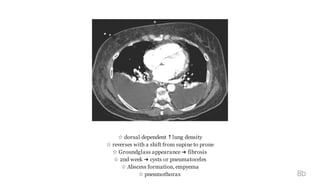

CT in ARDS

8a

☆ dorsal dependent ↑lung density

☆ reverses with a shift from supine to prone

☆ Groundglass appearance ➜ fibrosis

☆ 2nd week ➜ cysts or pneumatoceles

☆ Abscess formation, empyema

☆ pneumothorax 8b